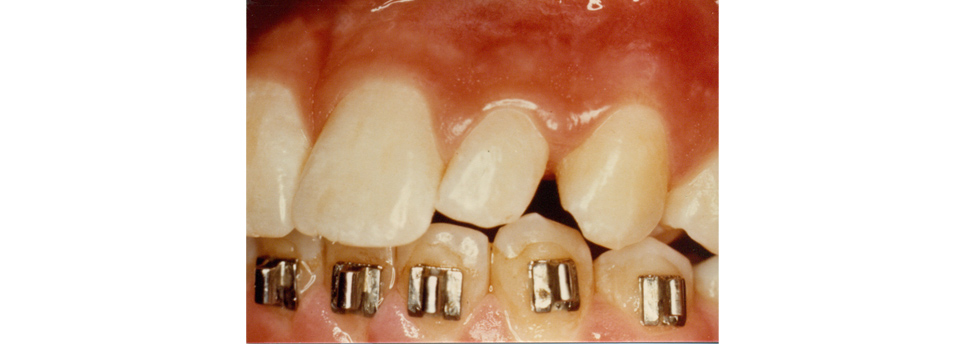

We enjoy working with children of all ages and feel it is very important to begin dental health early. Our patients are 3 years and up. Many dental problems can be intercepted and treated easily if diagnosed early. Our office offers sealants, fillings, crowns, extractions on “baby” teeth and adult teeth. We offer screening for future orthodontic treatment and have a wonderful team of specialists to help make difficult cases easy. Click here to find out more.